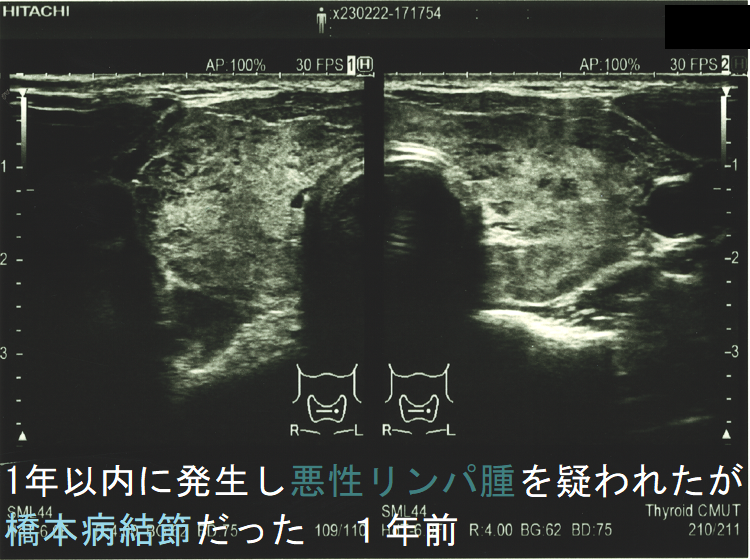

![1年以内に現れ悪性リンパ腫が疑われたが橋本病結節だった 1年前 (水平断)[拡大] 1年以内に現れ悪性リンパ腫が疑われたが橋本病結節だった 1年前 (水平断)[拡大]](../images/special/thyroid2/images20251130213537.png)

橋本病(慢性甲状腺炎)ではリンパ球浸潤に伴う炎症から濾胞細胞の好酸性変性[好酸性細胞(Hürthle細胞,ハーテル細胞)]・過形成、浮腫、線維化で結節性病変を形成[結節性橋本病(橋本病結節)]。病理学的に腺腫様甲状腺腫・腺腫様結節と同じで、橋本病(慢性甲状腺炎)を基盤とする腺腫様甲状腺腫・腺腫様結節。超音波(エコー)検査では内部が極めて低エコーのため甲状腺癌、甲状腺原発悪性リンパ腫と鑑別必要。細胞診では好酸性細胞、リンパ球集簇、炎症性多核巨細胞を認め、甲状腺乳頭癌ワルチン腫瘍型、通常型甲状腺乳頭癌・亜急性甲状腺炎と鑑別要。

橋本病(慢性甲状腺炎)では、リンパ球浸潤に伴う炎症から、濾胞細胞の好酸性変性・過形成、浮腫、線維化などの変化で結節性病変が形成されます[結節性橋本病(橋本病結節)]。病理学的には腺腫様甲状腺腫・腺腫様結節と同じ事で、橋本病(慢性甲状腺炎)を基盤とする腺腫様甲状腺腫・腺腫様結節になります。